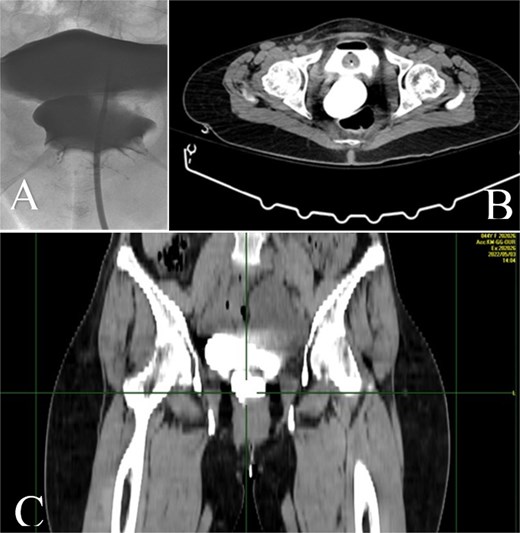

Intraoperatively, fibrotic adhesions were found and the lower part of right ureter was found clamped with the vaginal stump and bladder and an ureterocystotomy with antireflux ureter reimplantation were performed. Detachment of the ureter from the vagina was performed, using part of the peritoneum to seal the detached area, in order to prevent further fistula formation and the bladder wall was closed in two layers and a transurethral catheter was placed (Fig. 3).

The 3D image of reimplantation of the right ureter with antireflux technique in the dome of the bladder.